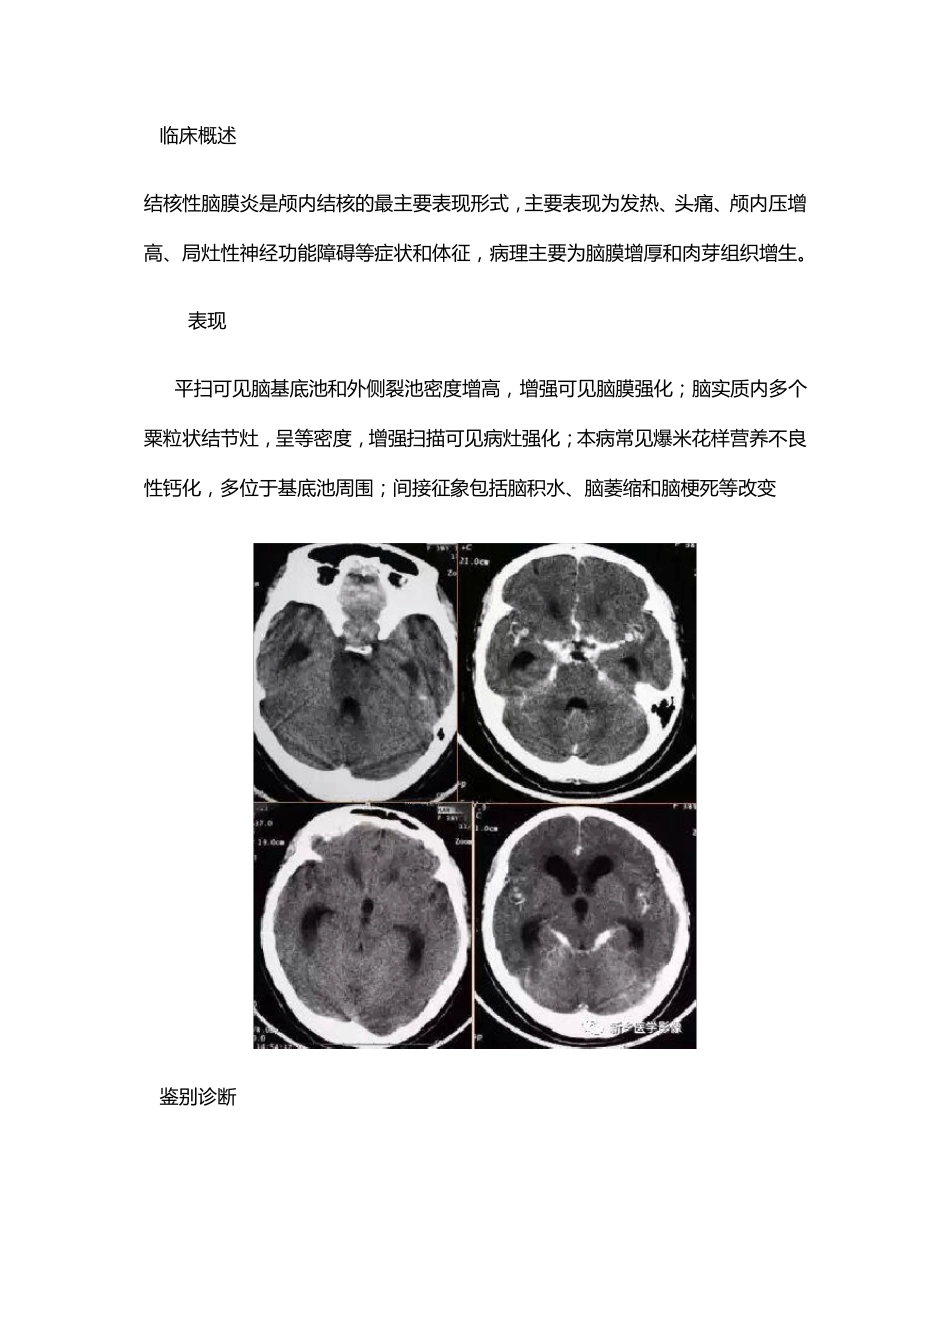

化 脓 性 脑 膜 炎 1.临 床 概 述 化 脓 性 脑 膜 炎 是 常 见 的 中 枢 神 经 系 统 化 脓 菌 感 染 性 疾 病 ,主 要 表 现 为 发 热 、头痛、惊厥和颅内压增高等。 2.CT表 现 平扫可见 基底池和脑 沟的 正常 形态消失, 呈等密度改变, 这是 由于炎 性 渗出物填充脑 池和脑 沟所致;增强扫描可见 脑 膜 强化 ;本病 可并发 脑 积水, CT表 现 为 脑室扩大;本病 可并发 硬膜 下积液, CT表 现 为 脑 外新月形低密度区;本病 并发 脑静脉窦血栓时, 增强扫描可见 典型空三角征, 此征象由强化 的 血流和血管壁与不增强的 血栓共同组成;可并发 出血性 脑 静脉梗死、脑 炎 或脑 脓 肿。 3.鉴 别 诊 断 脑 膜 转 移 : 脑 膜 转 移 灶 可 沿 脑 膜 呈 侵 润 性 生 长 , 并 可 在 局 部 形 成 肿 块 , 还 可 同 时伴 发 脑 内 转 移 , 病 灶 分 布 不 连 续 。 结核性 脑 膜 炎: 多数呈 亚急性 起病 , 常有结核接触史, 分 布 以基底池为明显, 并可 见多发 粟粒状结节灶 。 4.化脓性 脑 膜 炎患者行脑 脊液检查时 可 见脑 脊液外观浑浊, 白细胞增多, 以中性粒细胞为主, 细胞涂片或培养可 找到病 原菌。 结核性 脑 膜 炎 1.临 床 概 述 结 核 性 脑 膜 炎 是 颅 内 结 核 的 最 主 要 表 现 形 式 , 主 要 表 现 为 发 热 、头痛、颅 内 压增高、局灶性 神经功能障碍等症状和体征, 病理主 要 为 脑 膜 增厚和肉芽组织增生。 2.CT表 现 CT平扫可见脑 基底池和外侧裂池密度增高, 增强可见脑 膜 强化;脑 实质内 多个粟粒状结 节灶, 呈等密度, 增强扫描可见病灶强化;本病常见爆米花样营养不良性 钙化, 多位于基底池周围;间接征象包括脑 积水、脑 萎缩和脑 梗死等改变 3.鉴别诊断 脑 膜 转 移 : 脑 膜 转 移 灶 可 沿 脑 膜 呈 侵 润 性 生 长 , 并 可 在 局 部 形 成 肿 块 , 还 可 同 时伴 有 脑 内 转 移 , 病 灶 分 布 不 连 续 。 化 脓 性 脑 膜 炎 : 多 急 性 起 病 , 常 见 脑 积 水 和 硬 膜 下 积 液 改 变 。 4.结 核 性 脑 膜 炎 患 者 行 脑 脊 液 检 查 示 细 胞...